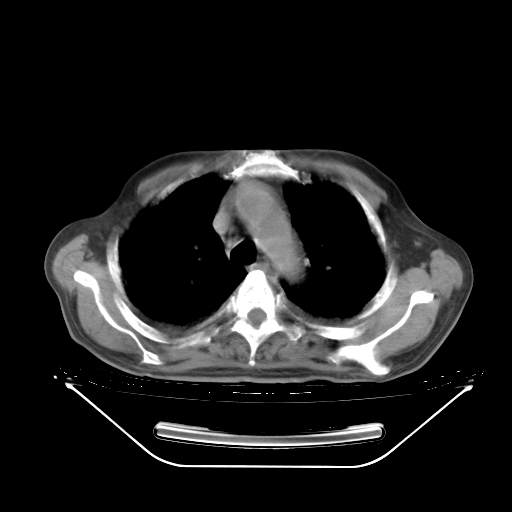

今天复查肺部CT,发现双肺广泛磨玻璃样改变。所以我把3月19日和5月9日相隔50天的肺部CT上传。请大家会诊。

2009年3月19日肺部CT片。

2009年3月19日肺部CT

胸腹部CT,诊断意见:左上肺叶钙化灶、左侧胸膜局限性增厚并钙化、胆囊炎。描述部分肺组织呈磨玻璃样改变。